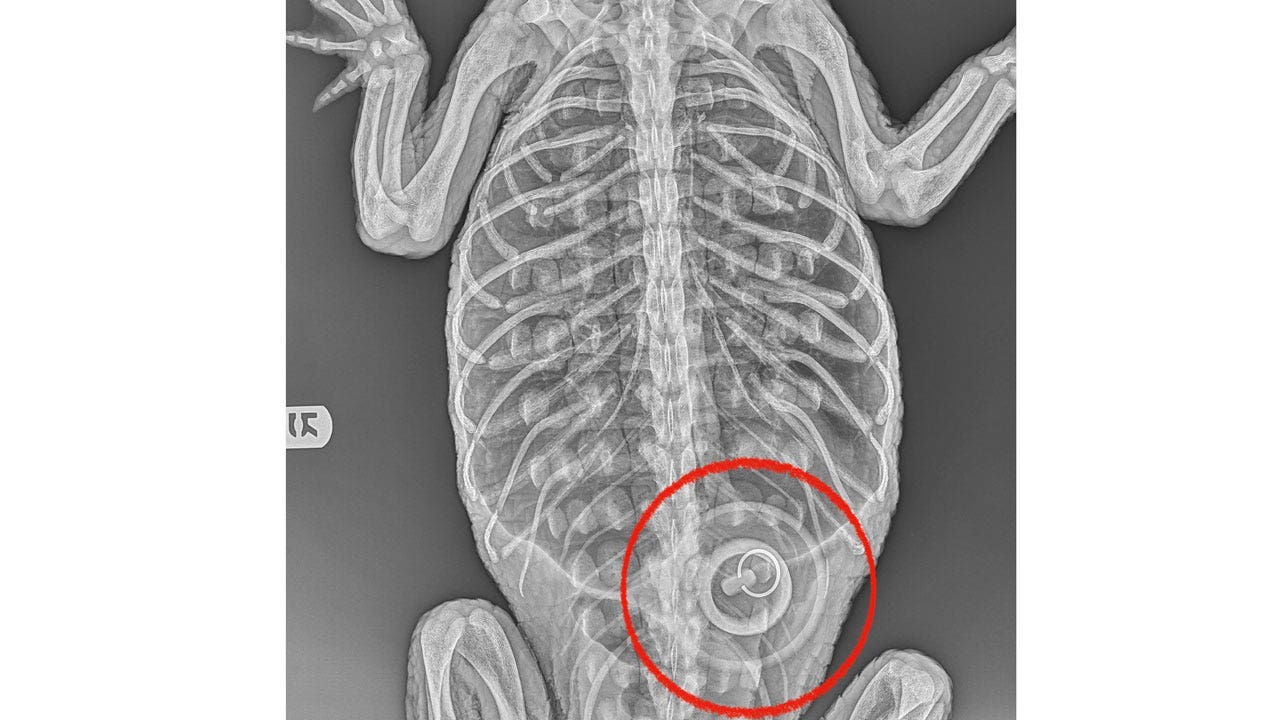

U.S. 3 hours ago Alligator found in NYC lake swallowed bathtub stopper The almost five-foot-long alligator found in a New York City lake reportedly swallowed a bathtub stopper, according to a spokesperson for the Bronx Zoo.